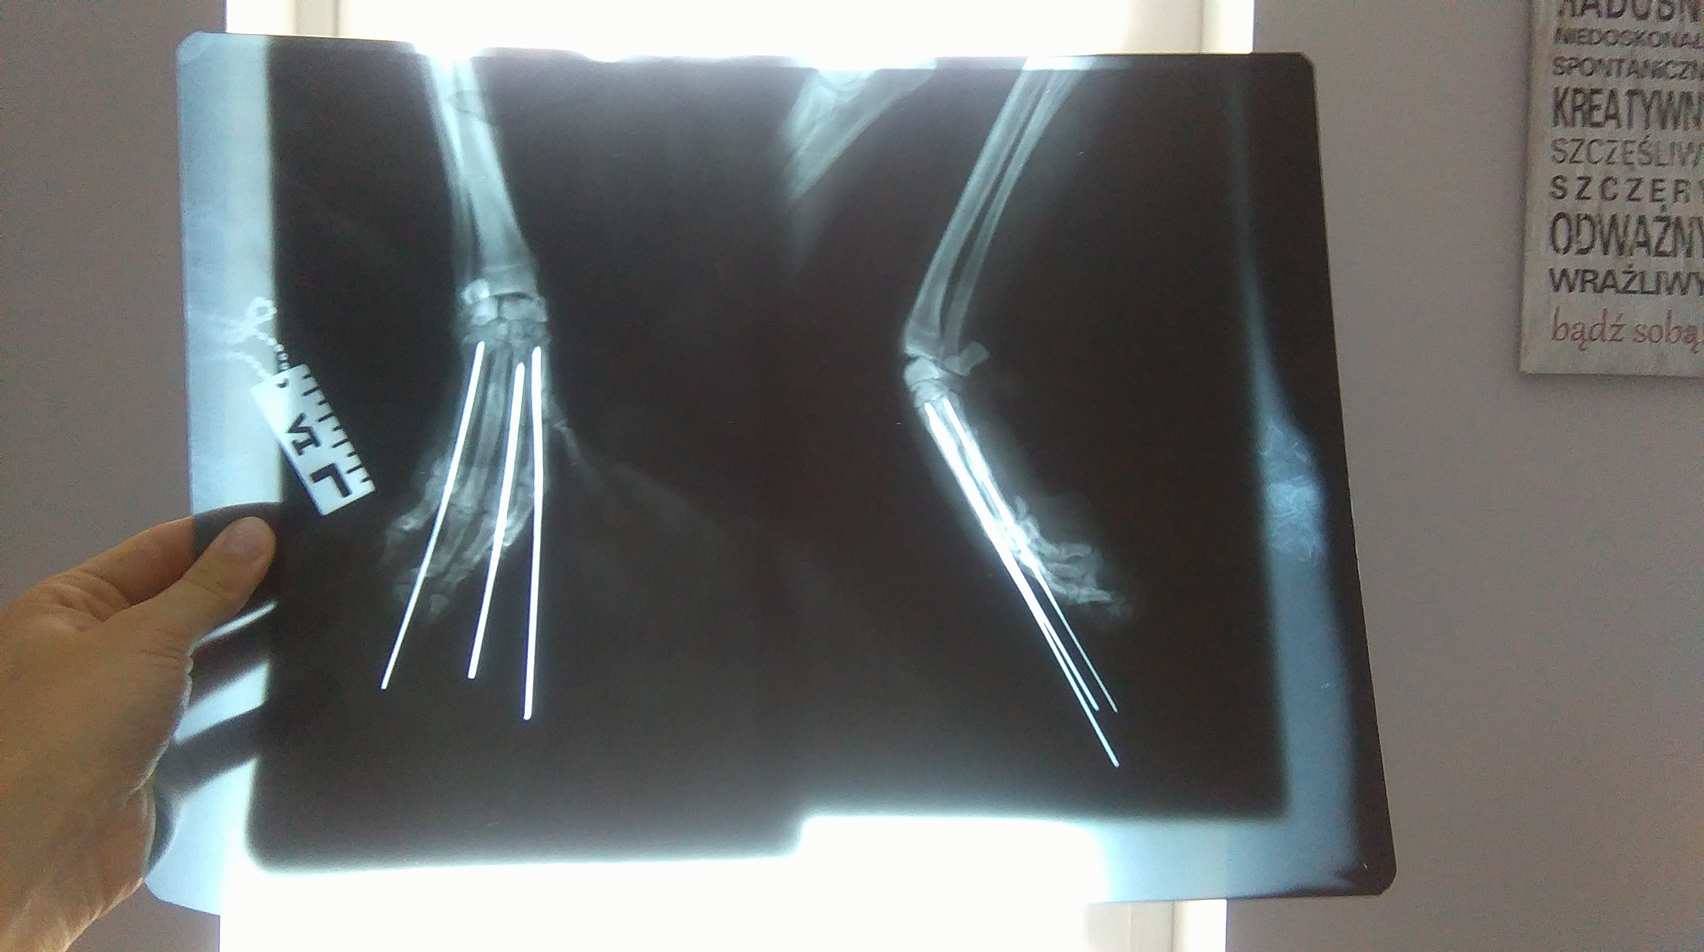

Żuczek został porzucony w jednej ze Świętokrzyskich wsi. Błąkał się kilka miesięcy w poszukiwaniu jedzenia. Któregoś dnia zmęczony tułaczka zasnął na skraju ulicy i wtedy właśnie auto przejechało mu łapkę!! Biedak czekał aż 2 dni na zbawienie. 23 czerwca został od razu został przewieziony do całodobowej kliniki w Radomiu, na miejscu zostało zrobione prześwietlenie, podano również leki przeciwbólowe. RTG wykazało złamanie trzech z czterech kości śródręcza, konieczna była operacja mająca na celu zespolenie złamanych kości za pomocą gwoździ chirurgicznych. operacja odbyła się następnego dnia, lekarze z cudem poskładali maleńkie kosteczki Żuczka. Przez okres 3 tygodni Żuczek miał założony lekki opatrunek, konieczna była codzienna toaleta rany oraz maksymalne ograniczenie ruchu dlatego psiak zamykany była w klatce kenelowej. Po okresie 3 tygodni udalismy się na kontrolę, niestety weterynarze uznali że Żuczek krzywo stawia łapę, dlatego konieczne było założenie opatrunku gipsowego na okres 4 tygodni. Po długim okresie noszenie całej łapki w gipsie została założona cienka warstwa tworzywa którą Żuczek nosi do dziś. Śródręcze zostało odsłonięte po to aby psiak po woli zaczął stawać na łapkę.

Faktura za operację Żuczka wyniosła ponad 1000 zł, do tego dochodzą bieżące wydatki które łącznie dają naprawdę ogromną sumę, ale jak inaczej mogliśmy postąpić kiedy ten pies niemalże konał z bólu?!